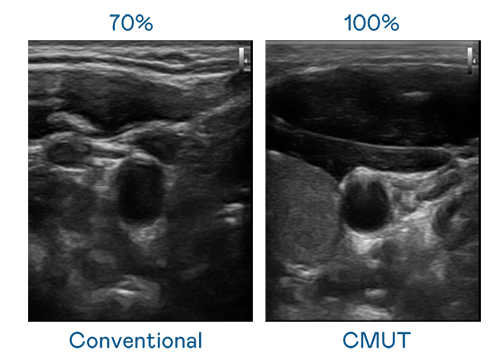

CMUT 技术是一种用电容式微机电元件来产生超音波讯号的技术。与传统 PZT 压电式技术相比,CMUT 频宽增加 30%,更宽频的超音波讯号让影像解析度大幅提升,是实现高影像品质医疗超音波扫描、促进精准医疗发展的关键技术。

超音波影像的解析度高低,首先取决于探头能发出的讯号频宽。YABO鸭脖 CMUT 可提供高清晰的超音波讯号,提供高频宽、高灵敏度、影像纹理细节更高的超音波影像,协助医护人员缩短影像判读时间及利用精准的医疗影像进行诊断。